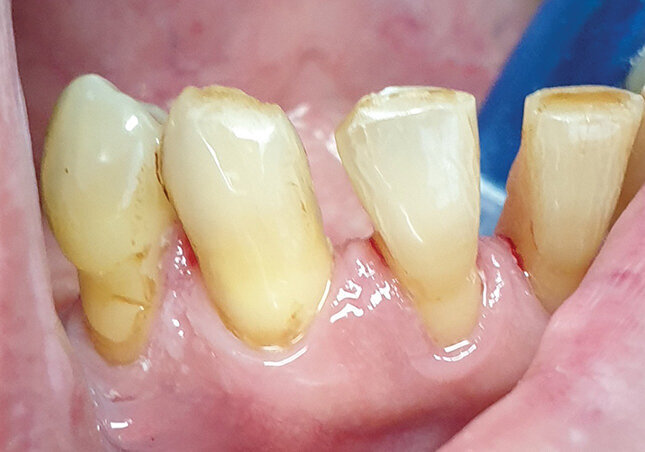

Pacijent B, kontrola nakon dva meseca. Pacijent B pušač, koja ni nakon 2 meseca nije uspeo u potpunosti u odvikavanju od svoje loše navike. Čvrsta komponenta duvanskog dima, u funkciji vremena od 2 meseca, pokrila je još veću površinu zuba, u vidu estetski neprihvatljivih pušačkih pigmentacija, čija je lepljivost i hrapavost pogodovala zadržavanju dentalnog plaka i formiranju zubnog kamenca. Slike se koriste kao dodatni motiv pacijentu B u odvikavanju od pušenja (Sl. 2.3).

Sl. 2.3: Pacijent B, kontrola nakon 2 meseca pušenja cigareta